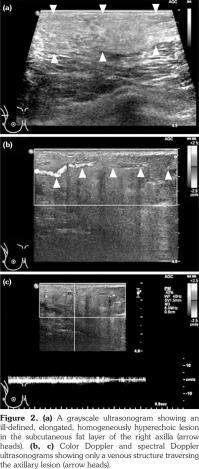

Full-field digital mammography was performed (MAMMOMAT Inspiration; Siemens AG, Munich, Germany). A right mediolateral oblique view revealed an asymmetric density in the right axilla (Figure 1). Ultrasonography was performed with a 5- to 12-MHz linear transducer (iU22; Philips Medical Systems, Bothell, WA, USA), which identified a poorly defined, elongated, homogeneously hyperechoic lesion in the subcutaneous fat layer of the right axilla (Figure 2). The lesion did not exhibit increased vascularity, except for a normal traversing venous structure (Figure 2). The lesion was surgically excised. Pathological examination confirmed the diagnosis as lipogranuloma (Figure 3). On the other hand, complete blood test results were normal.

In the breast, lipogranulomas have been reported after the release of the silicone gel from breast implants, after the application of a traumatic treatment called “Bu-Hwang,” and after phenothiazine therapy.(8,9) The mammographic features of lipogranuloma have been described in only two cases. These cases presented a bizarre-shaped lesion with bright density which proved to be lipogranuloma with osseous metaplasia and an irregular mass containing several microcalcifications.(8,10) The ultrasonographic features of breast lipogranuloma have been described in only one case, which presented an ill-defined hyperechoic lesion.(10)

Besides the breast and axilla, the ultrasonographic features of lipogranuloma have been described in the penis and scrotum, and have included cases with an ill-defined area of increased echogenicity in the subcutaneous tissue of the penile shaft,(11) a poorly defined extratesticular echogenic mass with an elongated appearance on a longitudinal scan,1 and an intratesticular heterogeneously hypoechoic mass.(12)